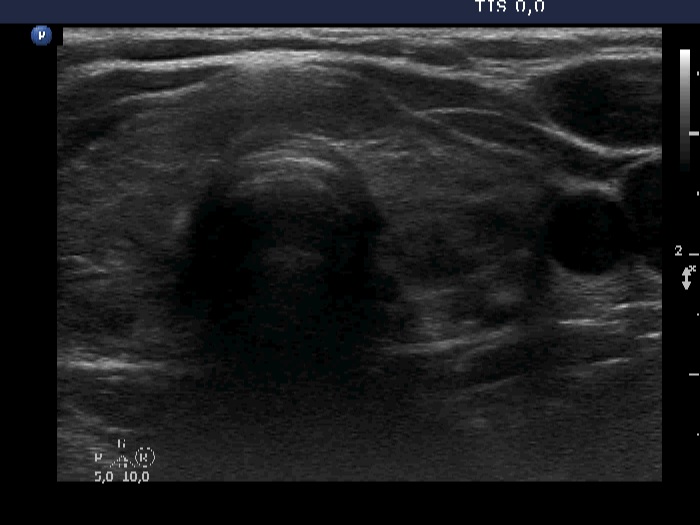

Consecutive patients with the final diagnosis of Hashimoto's thyroiditis - case 2 (23) (ultrasonographic picture 5)

Left lobe, transverse scan. The pattern is similar to that of the contralateral lobe.